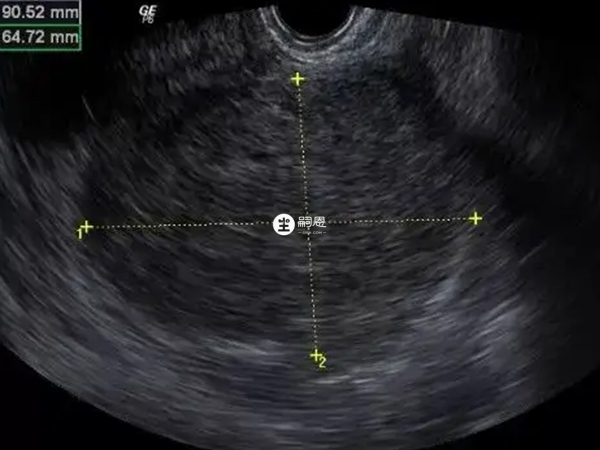

患有多發性子宮肌瘤,三年前行剔除術,現復發。然後現在還有三個凍胚,B超顯示子宮內膜無血流,子宮內膜容積血流0,我也是醉了。不知道是不是因為這幾天呆在家完全不運動的原因,子宮血流不好,但最後還是決定移植,看緣分吧。想問問大家是不是子宮內膜血流不好0級真的會影響胚胎著床啊?子宮內膜血流不好0級就是會影響胚胎著床,因為子宮內膜血流0級就是無血流,沒有供血的話,就不利於胚胎著床。子宮內膜血流分級就是指血管進入子宮內膜的深度,移植前查出子宮內膜血流不好0級是不能移植的,而子宮內膜血供較差,如果是宮腔粘連、內膜對雌激素不敏感或抵抗,導致的子宮內膜進行血供減少是可以調理改善的,如果是栓塞引起的內膜血流不好,是沒有辦法改善的。所以說,子宮內膜血流不好0級建議先調理,不然就會影響胚胎著床。

子宮內膜內及內膜下血流均可探測到的患者,其試管移植後妊娠率及胚胎種植率明顯提高,活產率明顯提高,流產率明顯降低。所以說,子宮內膜血流不好0級肯定是會影響胚胎著床的。也有研究發現,IVF-ET週期妊娠與非妊娠的患者相比,子宮內膜下血流S/D、PI、RI無差異,只是缺乏子宮內膜下血流者就會種植失敗。